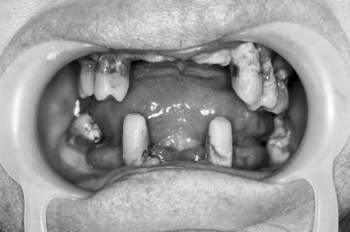

Родионов Артем Геннадьевич принимает в «Сеть стоматологических клиник ЭКСТРОДЕНТ» в Пушкине. Стаж 17 лет. Специализируется на хирургии и имплантологии, по которым клиника оказывает 16 услуг. Имеет 2 работы до/после в портфолио. Квалификация специалиста подтверждена 34 лицензиями, сертификатами и наградами.

2 работы в портфолио